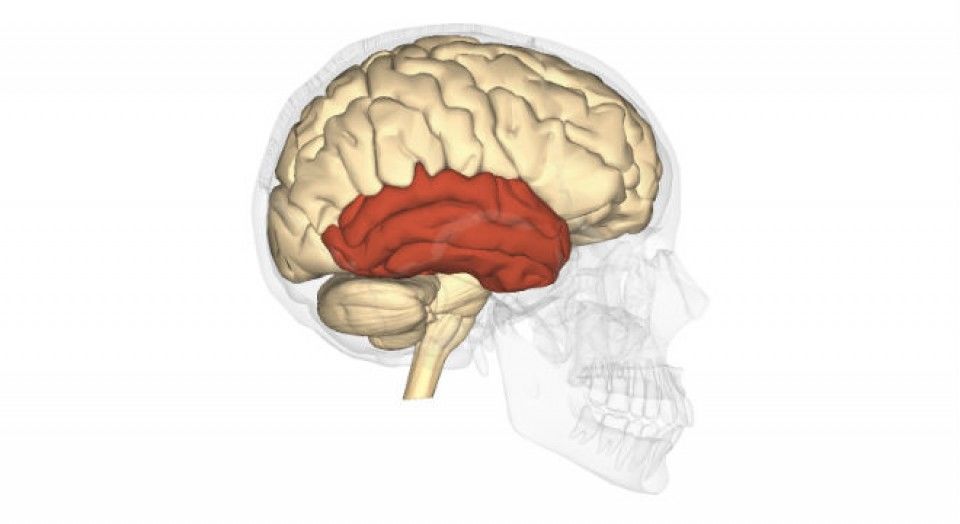

Tálamo001 (image/jpeg)